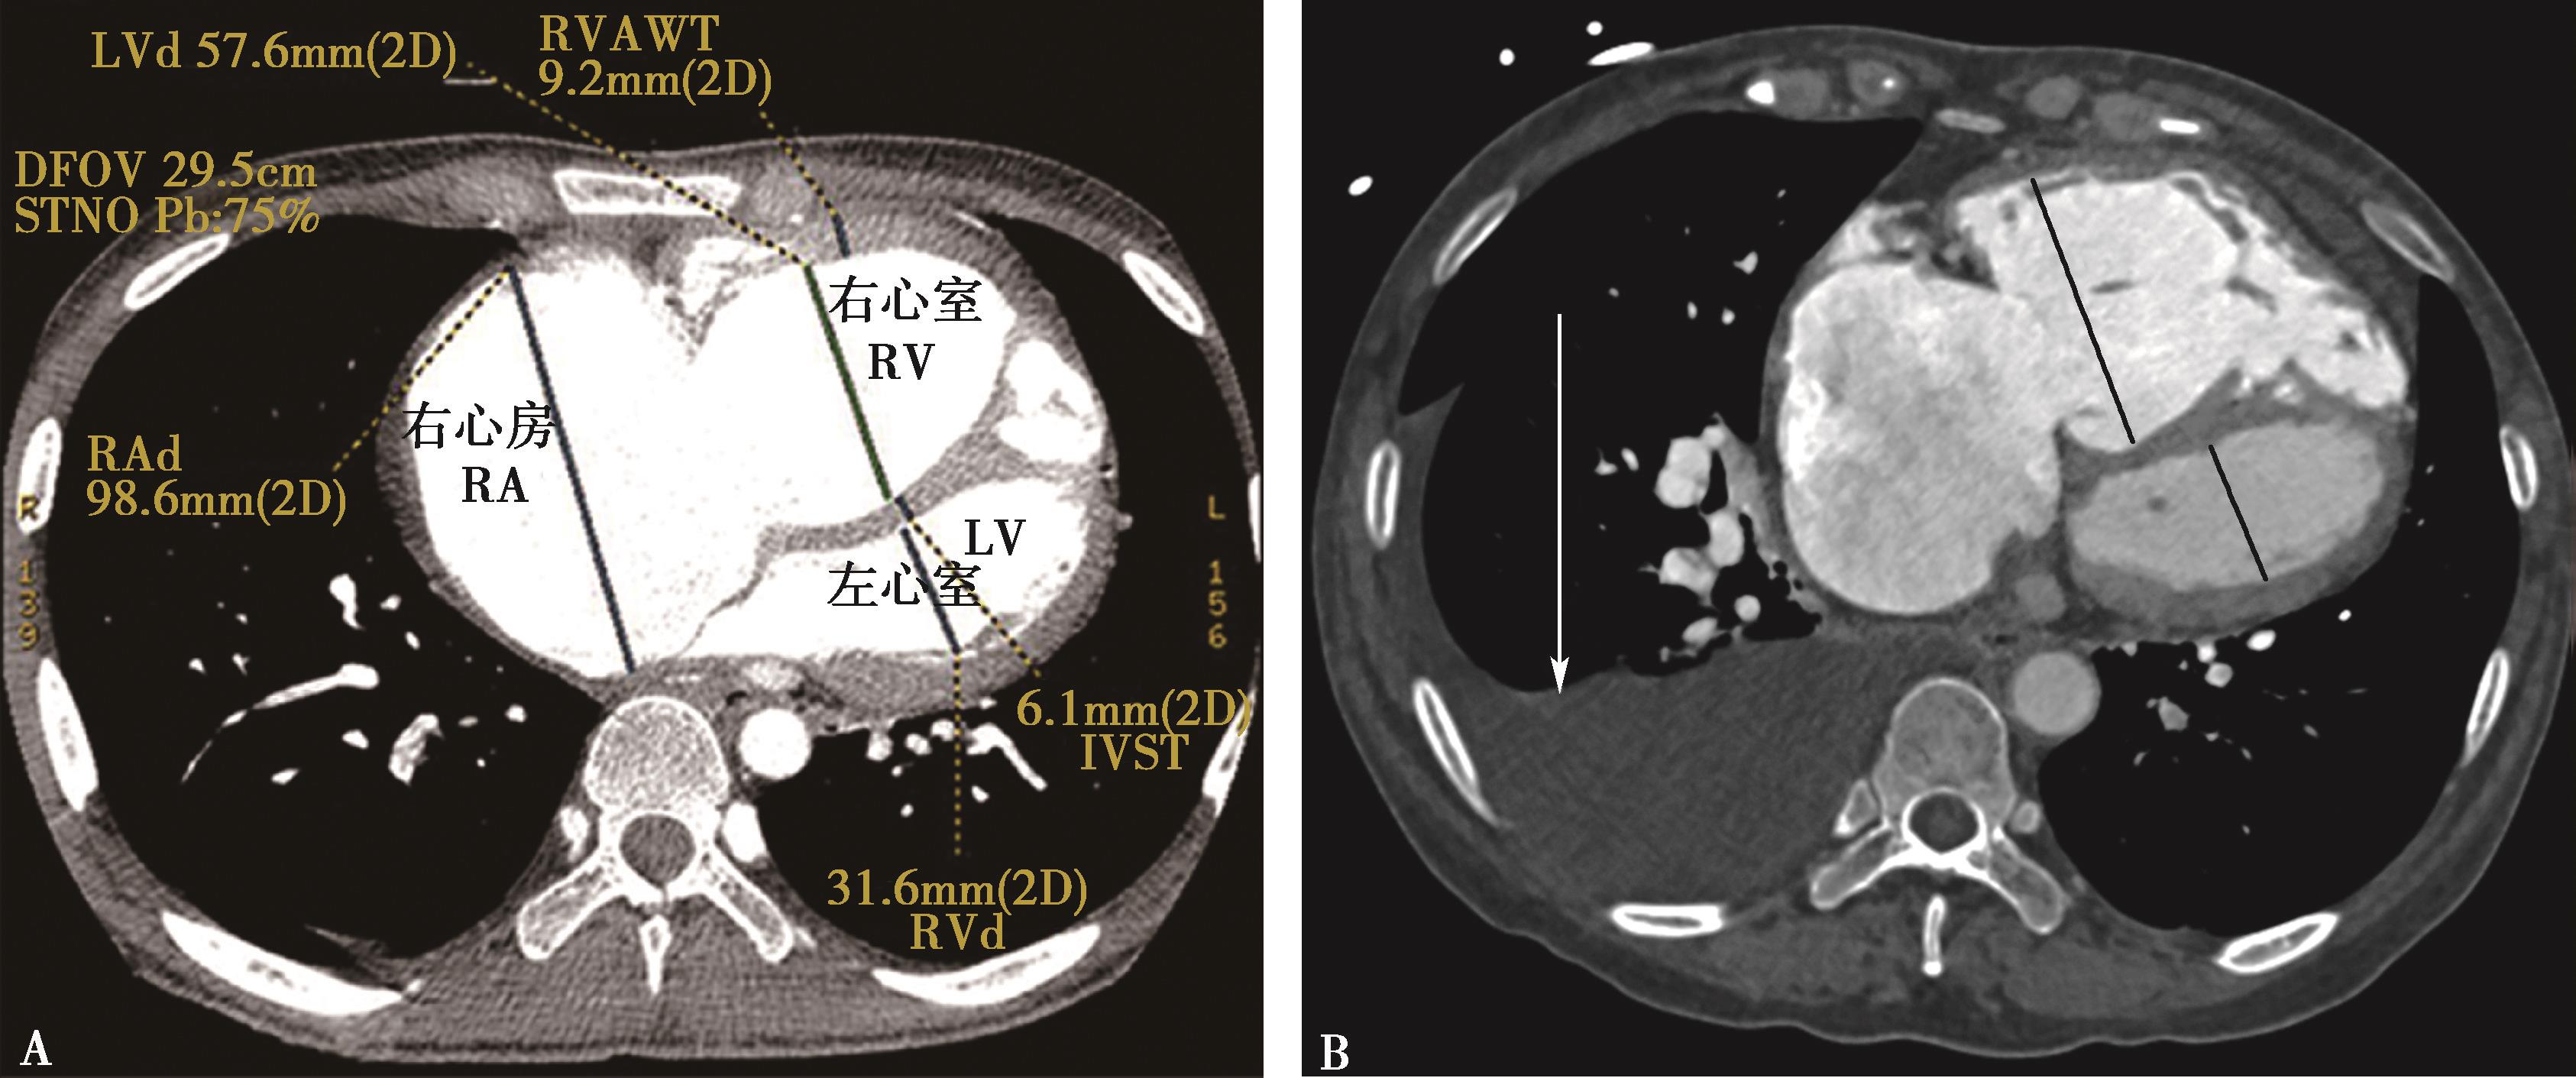

(三)多排螺旋CT右心功能评价

1.右心室增大

横断像心室最大层面测量左右心室最大横径(图8-3-10),正常心脏右心室横径:左心室横径<1,(a∶b<1),室间隔居中(红色↑)。右心室增大,右心室横径:左心室横径>1,(a∶b>1),室间隔凸向左心室(红色↑)。

2.右心室增大心脏顺钟向转位

横断像心室间隔与纵轴夹角可以反映右心室增大;由于右心室增大,心脏顺钟向转位,室间隔与纵轴夹角增大(图8-3-11)。

图8-3-10 横断图像

A.正常心脏,a∶b<1; B.右心室增大,a∶b>1

图8-3-11 横断图像

A.正常心脏;B.右心室增大,顺钟向转位,室间隔与纵轴夹角增大(↑)

3.CTPA对右心功能不全(RVD)的定性及定量诊断标准目前尚无定论,较为公认的定性诊断方法是右心室增大,即右心室最大短轴横径(RVd)超过左心室最大短轴横径(LVd)。文献报道横切位图像上心脏的量化测量指标,RVd和LVd,特别是RVd/LVd,与肺栓塞的严重程度和死亡呈正相关(RVd,RVd/LVd)或负相关(LVd)。在对25例肺栓塞和14例大面积肺栓塞患者的研究中,Contractor等和Lim等发现以超声心动图为参考标准,CTPA对RVD(诊断标准为RVd/LVd>1和/或室间隔移位)的诊断敏感性为78%~92%,特异性为100%,阳性预测值为100%。Araoz等的研究认为,与右心室大小正常的肺栓塞患者相比,RVd/LVd>1的肺栓塞患者进入重症监护室的危险度高3.6倍。多项研究也认为RVd/LVd>1.5提示肺栓塞患者的病情严重。Collomb等的研究认为,通过分析CTPA显示的肺动脉树的阻塞程度、左心室最大短轴直径、右心室/左心室最大短轴直径比和主肺动脉直径,可以对肺栓塞患者血流动力学损害的严重程度进行评价。因此,RVd/LVd在肺栓塞患者的病情评价方面有着非常重要的临床意义。此外研究显示肺动脉高压患者,脊柱室间隔夹角与右心功能参数具有显著相关性,提示该角在评价肺动脉高压患者右心功能具有一定价值。

Cecilia研究报告,CT右/左心室径比值(dimensional ratio)>1.0评价右心室功能不全,是急性肺栓塞院内死亡及临床恶化的独立预测因子(HR 3.5,95%CI 1.6~7.7; P =0.002)。 急性肺栓塞右心室正常a∶b<1,无事件转归的阴性预测值为100%[95%可信区(CI)下限为94.5%]。